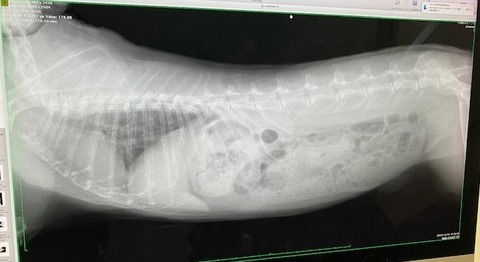

レントゲンなどは当初の去勢手術以降、機会がなかったので、

血液検査とともにしっかり健診させていただきました。

レントゲン

歯根への影響も見られず、共に良好でした